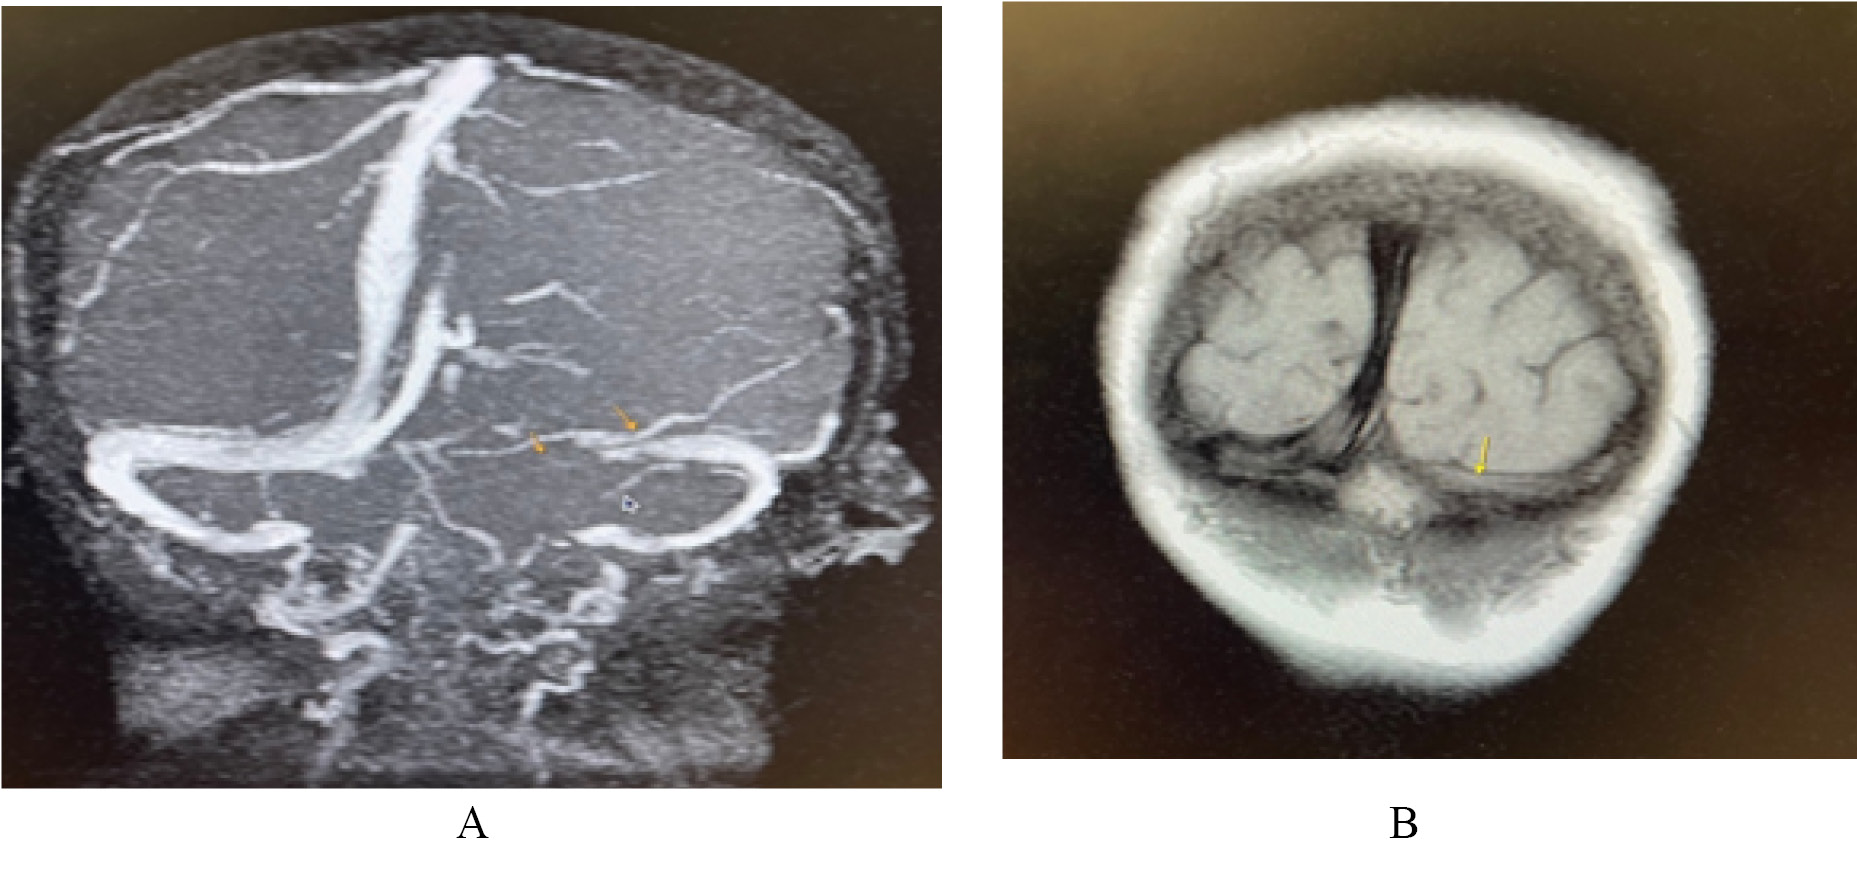

МР-веносинусография головного мозга от 07.09.2021 (рис. 3, 4).

Рис. 3. Магнитно-резонансная венографическая картина: отсутствие сигнала от кровотока по значительной части левого поперечного синуса (А), что не позволяет исключить тромбирование, либо замедление кровотока (Б), с учётом Cor N1 взвешенного изображения

Рис. 4. Магнитно-резонансные венографические признаки, подозрительные на единичный тромб в правом поперечном синусе (А). Однако, с учётом сырых данных (Б) и нативного Т2-взвешенного изображения, эти изменения являются арахноидальными грануляциями, врастающими в синус (В)